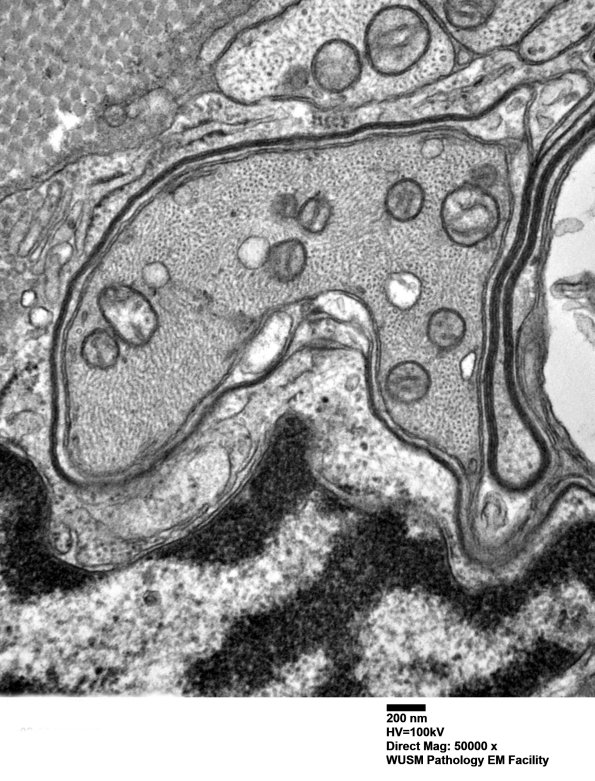

An early Schwann cell sheath has a delicate myelin surround of only a few turns. (electron micrograph)